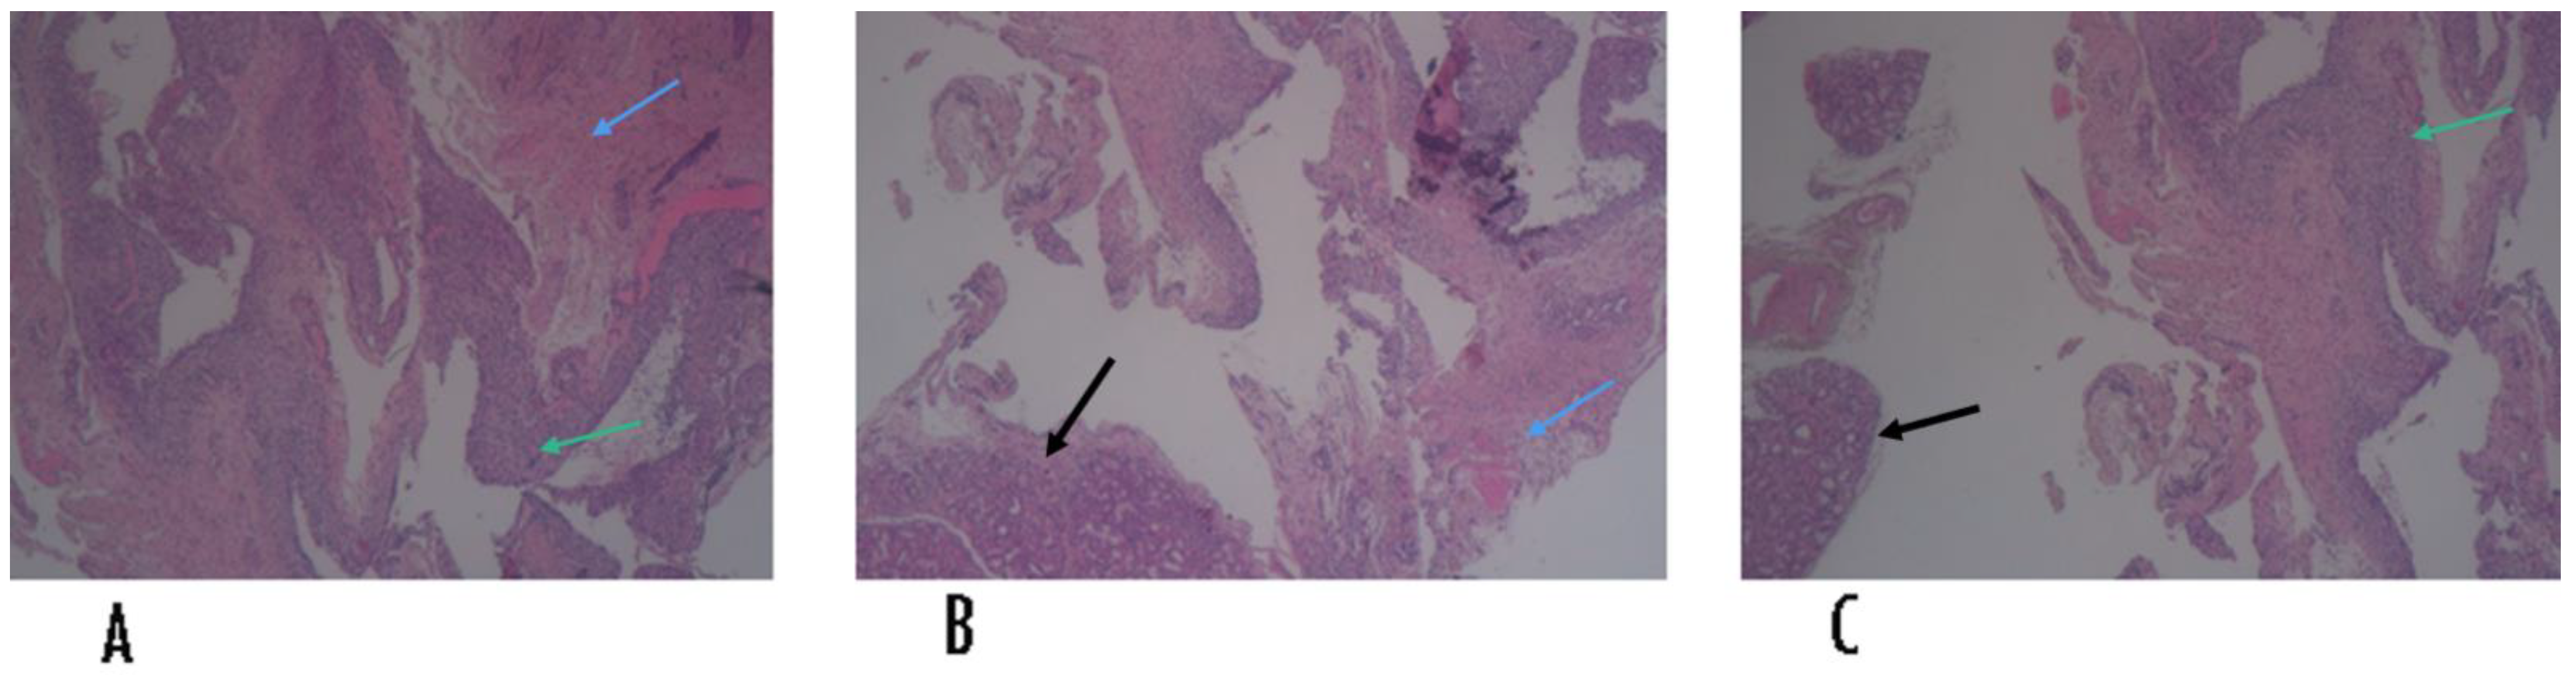

2. Case History

Surgical Procedure